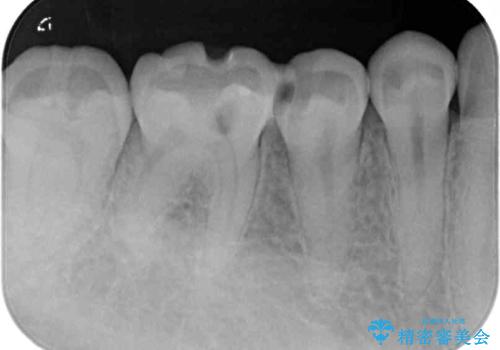

左上奥と右下奥に治療中の歯があり、虫歯を取っている途中で仮詰めの材料が充填されている状態でした。

仮詰め材を外すと虫歯が残っていたので、全てを取り除いた後に、ゴールドインレーの型どりを行いました。